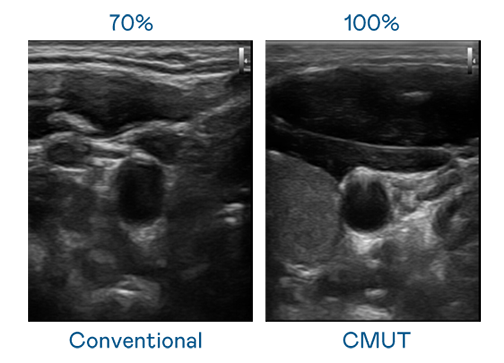

CMUT 技术是一种用电容式微机电元件来产生超音波讯号的技术。与传统 PZT 压电式技术相比,CMUT 频宽增加 30%,更宽频的超音波讯号让影像解析度大幅提升,是实现高影像品质医疗超音波扫描、促进精准医疗发展的关键技术。

大频宽带来超清晰影像

超音波影像的解析度高低,首先取决于探头能发出的讯号频宽。尊龙凯龙时官网 CMUT 可提供高清晰的超音波讯号,提供高频宽、高灵敏度、影像纹理细节更高的超音波影像,协助医护人员缩短影像判读时间及利用精准的医疗影像进行诊断。